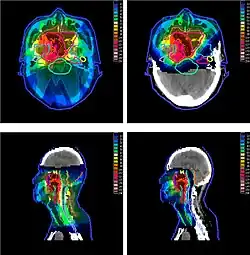

La planification de traitement est souvent — improprement — appelée dosimétrie. Il s'agit à l'aide de console informatique dotée d'un système de planification de traitement et d'images numériques du patient, le plus souvent des images scanner, de choisir une balistique de traitement et de calculer la dose délivrée dans les tissus en prenant en compte la prescription médicale au volume cible et les tolérances des organes à risque. Elle est réalisée par un physicien médical ou, par délégation de ce dernier, par un dosimétriste.

Les contours des volumes cibles et des organes à risques sont établis sur les images scanner du patient par le radiothérapeute[31]. Ils permettent d'obtenir des organes virtuels en trois dimensions sur lesquels auront lieu l'étape de simulation virtuelle[32]. La représentation en trois dimensions de ces volumes permet de visualiser en temps réel et pour toutes les orientations leurs géométries. On obtient donc un patient « virtuel ». La planification, réalisée sous la responsabilité du physicien médical, consiste à définir la balistique de traitement en choisissant le nombre de faisceaux qui seront utilisés, ainsi que leur orientation, leur porte d'entrée et la forme du champ d'irradiation pour se conformer au maximum autour du volume cible en épargnant les organes à risques.

La dose à délivrer est définie selon des critères médicaux par le médecin radiothérapeute[31]. Elle est indiquée dans le TPS. Les interactions rayonnement-matière y sont simulées pour calculer la distribution de dose dans le patient, à partir des images scanner. L'analyse de la balistique consiste à contrôler les histogrammes dose-volume, vérifier que les volumes cibles sont suffisamment couverts et que la dose aux organes à risques ne dépasse pas les contraintes médicales[34]. Les paramètres du choix de l'énergie, de l'orientation des faisceaux, ou de la forme des champs d'irradiation sont adaptés jusqu'à obtenir un résultat satisfaisant.

Une fois la planification du traitement terminée, celle-ci doit être validée conjointement par un physicien médical et un oncologue-radiothérapeute. Les deux professionnels se partagent la responsabilité de l'optimisation. Pour chaque patient, le médecin est responsable de la prescription (du diagnostic à la dose prescrite, en passant par la définition des volumes à irradier/protéger) et le physicien est responsable de la délivrance de la dose validée (de l'étalonnage des machines et des TPS jusqu'aux différentes étapes de calculs du plan de traitement, et de validations/vérifications nécessaires avant, pendant et après le traitement).